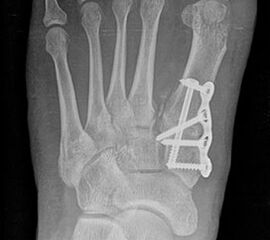

Bezüglich der Operationstechniken wird von früher häufig durchgeführten alleinigen Weich­teileingriffen am Großzehengrundgelenk aufgrund hoher Rezidivraten abgeraten 15. Die Operation nach Mc Bride mit lateralem Release, Exzision des lateralen Sesambeins, Abtragen der Pseudoexostose, Sehnenetransfer des M. adductor hallucis und mediale Kapselraffung zeigte unbefriedigende Mittel- und Langzeitergebnisse 16. Die Cerclage fibreux (mediale Kapselraffung) und das laterale Kapselrelease wird heute in Kombination mit einem knöchernen Eingriff angewendet. Bezüglich des Einsatzes von minimalinvasiven Operations­techniken vor Wachstumsabschluss liegen bisher keine Daten vor. Alle Osteotomien lassen sich nach Bedarf miteinander kombinieren. Es ist darauf zu achten, dass Osteotomien keine offenen Wachstumsfugen verletzen.

OP-Techniken

• Medial zuklappende Grundphalanxosteotomie nach Akin 17

• Subcapitale distale Chevron Osteotomie nach Austin 18

• Diaphysäre Osteotomie

• Scarf 19

• Ludloff 20

• Proximale Metatarsale I Osteotomien 21

• medial aufklappend – verlängernd

• lateral zuklappend – verkürzend

• bogenförmige Crescentic Osteotomie

• proximale Chevron Osteotomie

• proximale Verschiebeosteotomie

• medial aufklappende Cuneiforme I Osteotomie 1522

• Wachstumslenkung: Hemiepiphysiodese der lateralen Basisfuge am Metatarsale I  23

• Nach Schluss der Wachstumsfugen: TMT I Arthrodese nach Lapidus 2425